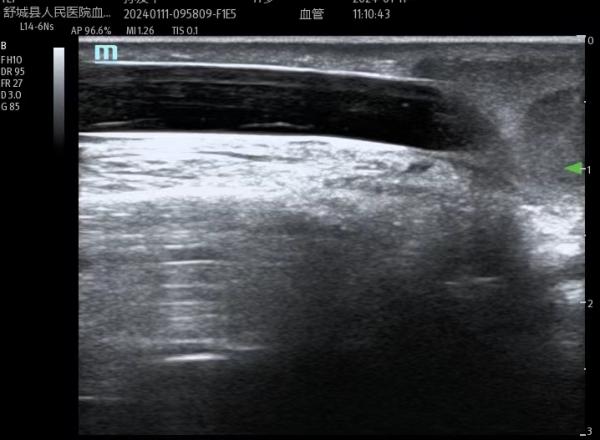

为了让血透患者生命线更通畅,针对疑难血管的穿刺,医护团队采用超声探头充分评估患者的血管方向,深度和血流量,精准定位可视化穿刺,最大限度减轻患者穿刺的痛苦,获得了很多患者的认可和肯定。为患者高品质透析,高质量生存保驾护航,我们一直在路上!